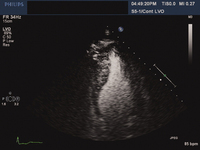

Dilated cardiomyopathy: echocardiogram

Tanejal AK, Wong J, Bayliss J. Antipsychotic-drug-induced dilated cardiomyopathy. BMJ Case Reports. 2009; doi:10.1136/bcr.09.2008.0958